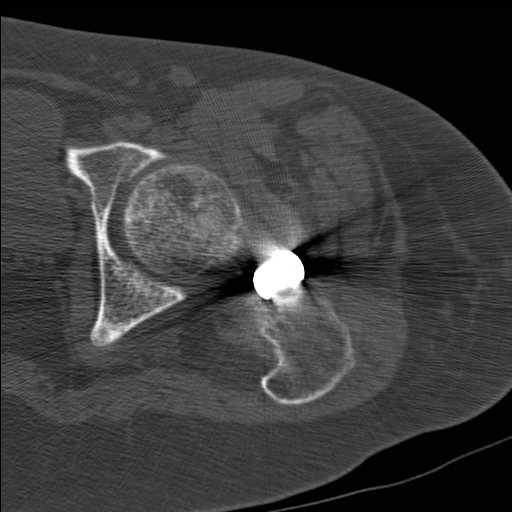

Добрый день уважаемые коллеги. Во такая ситуация. Девушка 19 лет травму получила в мае 2016г (изолированная травма, трансцервикальный перелом шейки левого бедра). Соматически здорова. Лечилась по месту жительства скелетным вытяжением в течении 1 месяца.

Затем переведена в наше учреждение. 18 июня выполнена операция, детали где , кто и как уточнять не имеет смысла( из протокола операции: выполнялась передняя артротомия, репозиция под визуальным контролем) . Учитывая характер выполненного остеосинтеза, после операции постельный режим 6 недель. Снимки в хронологии все выкладываю. КТ контроль сделан 2.09.16. для оценки состояния головки бедра. Помогите, определиться с дальнейшей тактикой.

согласен с Александром Николаевичем, надо пытаться сохранить сустав (в т.ч. его страдающее кровоснабжение. Судя по КТ Сохраняется ретроверсия шейки бедра. Вероятны трудности с репозицией последней. Для создания правильного направления шеечных винтов (Винта) возможно придется делать вальгусно-антекурвационную межвертельную остетомию, тем самым произвести разгибание в т/бедренном суставе проксимального отломка. И ретроверсия станет в большей степени вальгусом. То есть точка входа для гвоздя должна быть кзади от торчащей части прорезавшегося клинка со всеми вытекающими перемещениями проксимальной части.